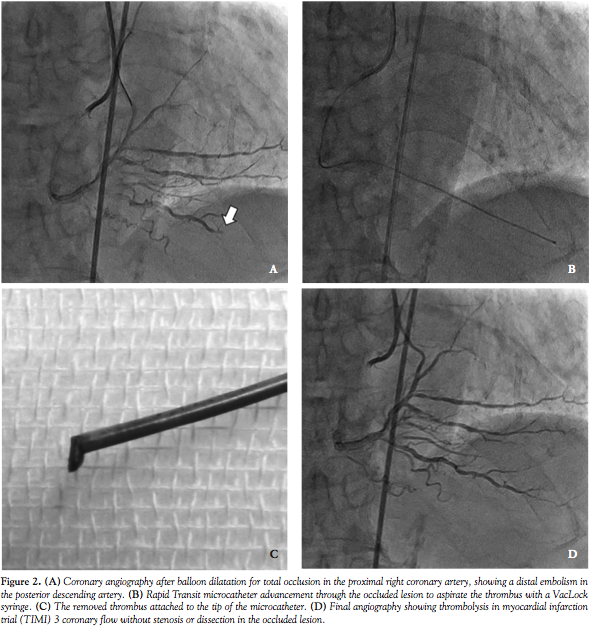

A 77-year-old man was admitted to our hospital with sudden chest pain. He had hypertension as a coronary risk factor. The electrocardiogram (ECG) showed ST-segment elevation in the inferior leads. One month before admission, he had undergone elective PCI because of unstable angina with severe stenosis in the right coronary artery (RCA). At that time, 2 Endeavor stents (Medtronic) were placed in segments #2 and #3. Emergency CAG upon hospitalization revealed total occlusion in the proximal Endeavor stent, which was placed in segment #2. A 6 Fr Launcher SAL 1.0 (Medtronic) was engaged in the RCA. The thrombus was aspirated with an Eliminate aspiration catheter (Terumo) after the lesion was crossed with a Runthrough guidewire (Terumo). Next, the lesion was well dilated with a 3.5 x 14 mm balloon catheter; however, the posterior descending artery showed occlusion in its mid-portion (Figure 2A). We therefore advanced the guidewire to the posterior descending artery, followed by a Rapid Transit microcatheter (Figure 2B). After retrieving the wire, we connected a VacLock syringe and drew the plunger. After confirming that aspiration was blocked, we slowly pulled back the microcatheter. We successfully removed the thrombus attached to the tip of the Rapid Transit microcatheter (Figure 2C). The final angiogram showed thrombolysis in myocardial infarction trial (TIMI) grade 3 flow without residual stenosis or dissection in the occluded artery (Figure 2D).